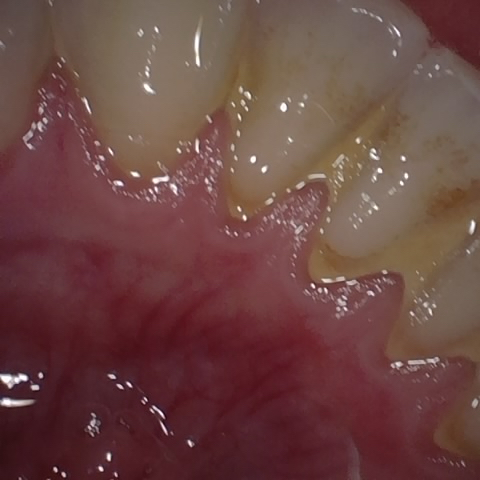

Annotated as "Good"